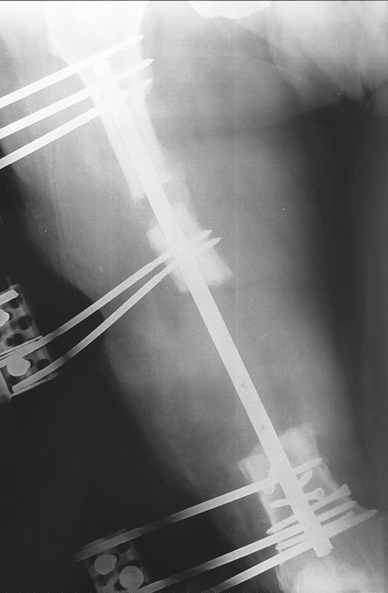

Appropriate radical debridement necessitates excision of all necrotic bone and soft tissues, and frequently causes instability at the involved extremity. The remaining bone and soft tissue defect has to be fixed and reconstructed. The distraction osteogenesis method of Ilizarov is used successfully for achievement of union, correction of the deformity, elimination of limb length inequality and reconstruction of segmental bone defects.

The duration of external fixation (external fixation index) depends on the amount of distraction required, and the extremity is prone to complications during this period. After the distraction phase is completed, the external fixator remains in place during the consolidation phase, which lasts twice as long as the distraction phase; but this period is hardly tolerated. If the external fixator is removed before sufficient consolidation is achieved, fractures, deformity and shortness will be the result. In our department, ‘lenghthening over nail’ method is used in order to decrease the external fixation index and increase patient comfort and activity level. In this method, the intramedullary nail is statically locked after the completion of the distraction phase, and external fixator is removed. The extremity is stabilized by the intramedullary nail during consolidation phase. In this way, complications due to long external fixation index or early removal of the external fixator are avoided.